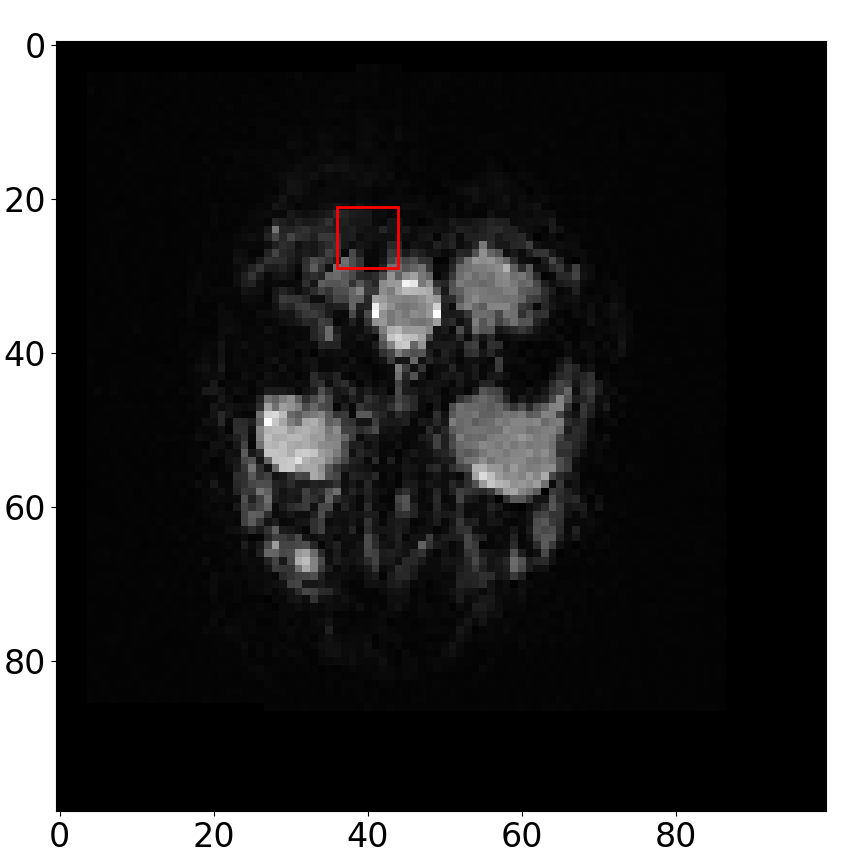

Fig. 4 depicts the results of the fMRI motion correction study. To illustrate this, we computed intensity values at specific voxels both before and after applying our SVR method, and we present these values over the time points that span the course of the fMRI series, where synthetic motion was introduced. The regions of interest (ROIs) from which we sampled voxels are depicted in Fig. 5. As observed, the intensity values after motion correction exhibit reduced variations compared to those before alignment and are more closely aligned with the intensity values of the reference volume.

Figure 4: fMRI motion-correction results. Sampled intensity values from various voxels across the registered volume (marked as AR - after registration), the motion-free volume (Vtsubscript𝑉𝑡V_{t}), and the volume with simulated motion (denoted as BR - before registration), collected over time points representing the course of the fMRI series. The voxels used in the analysis for the upper and bottom parts were sampled from the left and right red boxes in Fig. 5, respectively.

Refer to caption

Figure 5: ROIs of the selected pixels. From the highlighted red regions, we sampled voxels used for the fMRI motion correction experiment. The upper and bottom figures in Fig. 4 show results on voxels sampled from the left and right red boxes, respectively.